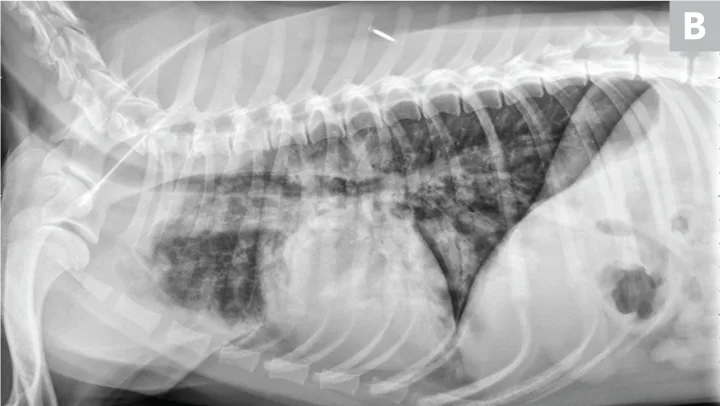

Dogs with bacterial pneumonia are typically presented with acute-onset coughing, lethargy, inappetence, and/or respiratory distress. An inflammatory leukogram and pyrexia, although common, are not always present. Radiographs may reveal an interstitial-to-alveolar pattern with a cranioventral distribution (Figure 1). Atypical distributions can also occur.5

FIGURE 1

(A) Bronchopneumonia. Cranioventral distribution of alveolar disease with air bronchograms. (B) A patchy distribution can be observed on the lateral projection. The changes overlying the heart may be missed in subtle cases.